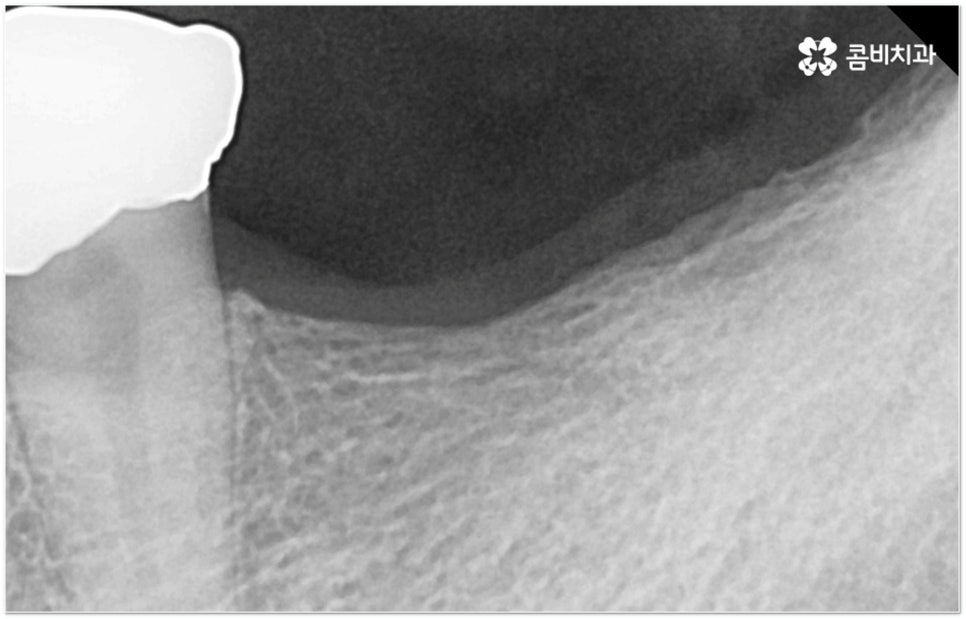

그러나 임플란트는 잇몸뼈에 직접 심어서 고정시키는 방식인 만큼 만약 환자분의 잇몸뼈가 부족하거나 치아가 빠진 후 오랜 시간이 지나 이미 잇몸뼈 소실이 상당 부분 이루어진 상태라고 한다면 먼저 골이식을 통해 이를 보충한 후 식립을 진행하는 뼈이식임플란트 방식을 이용할 필요가 있어요. 골이식 과정은 바탕이 되는 잇몸뼈의 밀도나 높이, 두께가 부족한 부분에 이식 재료를 심어주어 뼈를 재건해 주는 것인데 충분한 시간을 두고 무리하지 않게 진행하는 것이 뼈이식임플란트 수술의 성공률 및 안정적인 지속성을 높일 수 있는 방법이 될 거예요.

뼈이식임플란트 가 필요한지 살펴볼 때 3D CT 촬영과 같은 정밀 진단을 통해서 환자분의 잇몸뼈 두께 등 치조골 상태 뿐 만 아니라 구강 구조, 치아 및 잇몸 상태, 신경관 위치, 상악동까지의 거리 등을 꼼꼼하게 확인하여 치료 계획을 세우고 필요하다면 구강 질환에 대한 치료나 상악동 거상술 등을 선행하며 잇몸뼈 부족에 대해서도 골이식 과정을 먼저 진행하게 되는데요, 이러한 뼈이식임플란트 시술은 상당히 고난도의 복잡한 치과 진료인 만큼 관련 임상 경험이 풍부한 의료진과 함께 하는 것이 굉장히 중요하며 또한 수술 후 관리 면에서도 더욱 신경을 써 주시길 당부드리고 있어요.